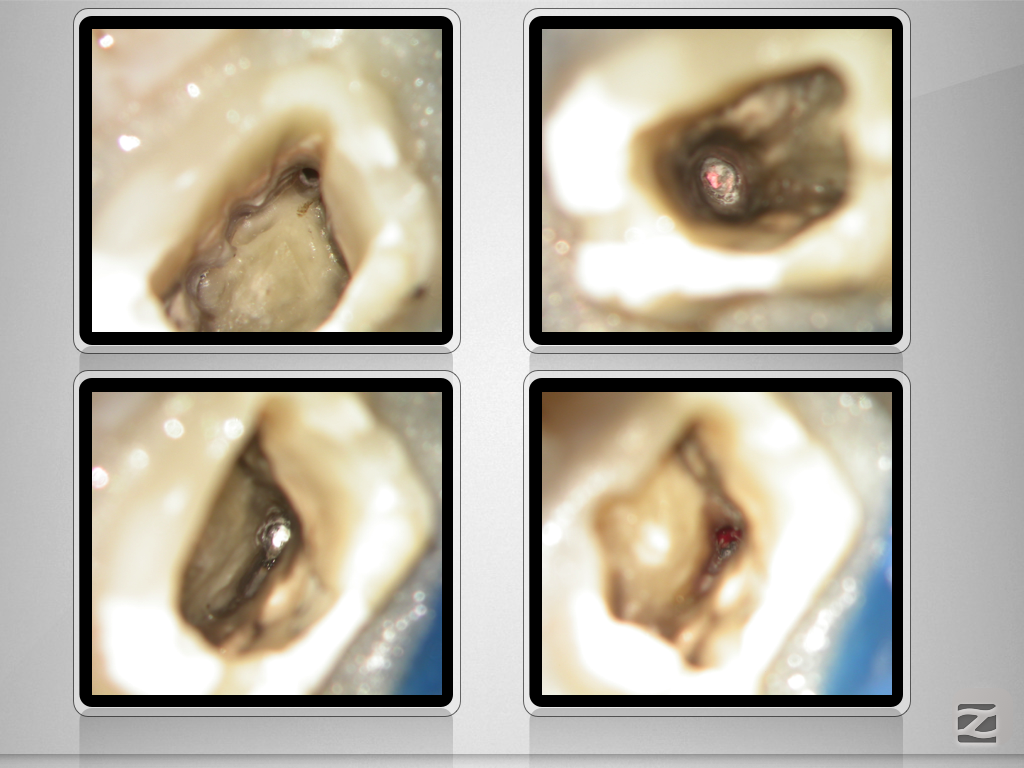

16d-007

Doppelt hält besser.